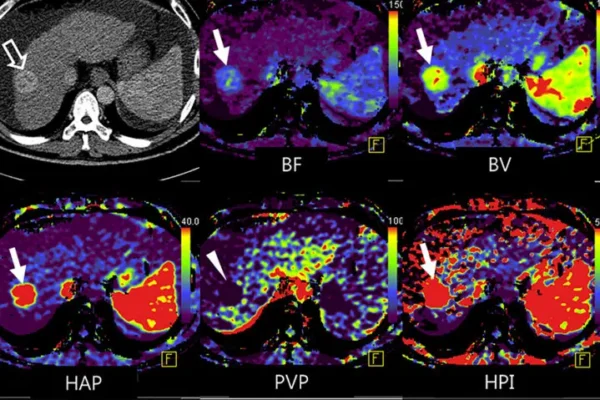

- Perfüzyon Emar